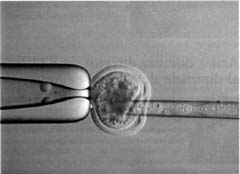

El inicio de la manipulación enzimática del material genético de los seres vivos y la aparición de la ingeniería genética molecular han permitido, a partir de 1970, el análisis bioquímico y molecular de los cromosomas, lo que ha dado lugar a una verdadera revolución biotecnológica que nos permite la manipulación de los seres vivos mediante la ingeniería genética en plantas (fijación biológica de nitrógeno, resistencia a parásitos o sequía, etc.) y animales (clonación, transferencia de embriones, etc.); diseñar estrategias racionales para el tratamiento y prevención de enfermedades (desarrollo de vacunas, uso de la técnica de ADN recombinante para diagnosis de enfermedades); obtención de células especializadas en la fabricación de productos de interés comercial y médico (producción de anticuerpos monoclonales, desarrollo de técnicas aplicadas a las industrias alimentaria, farmacéutica, química, etc.); mejoramiento de especies silvícolas y agrícolas (cultivo de tejidos vivos); recuperación y conservación de ecosistemas (bioinsecticidas y biodetergentes, control de contaminación ambiental y tratamiento de aguas residuales).